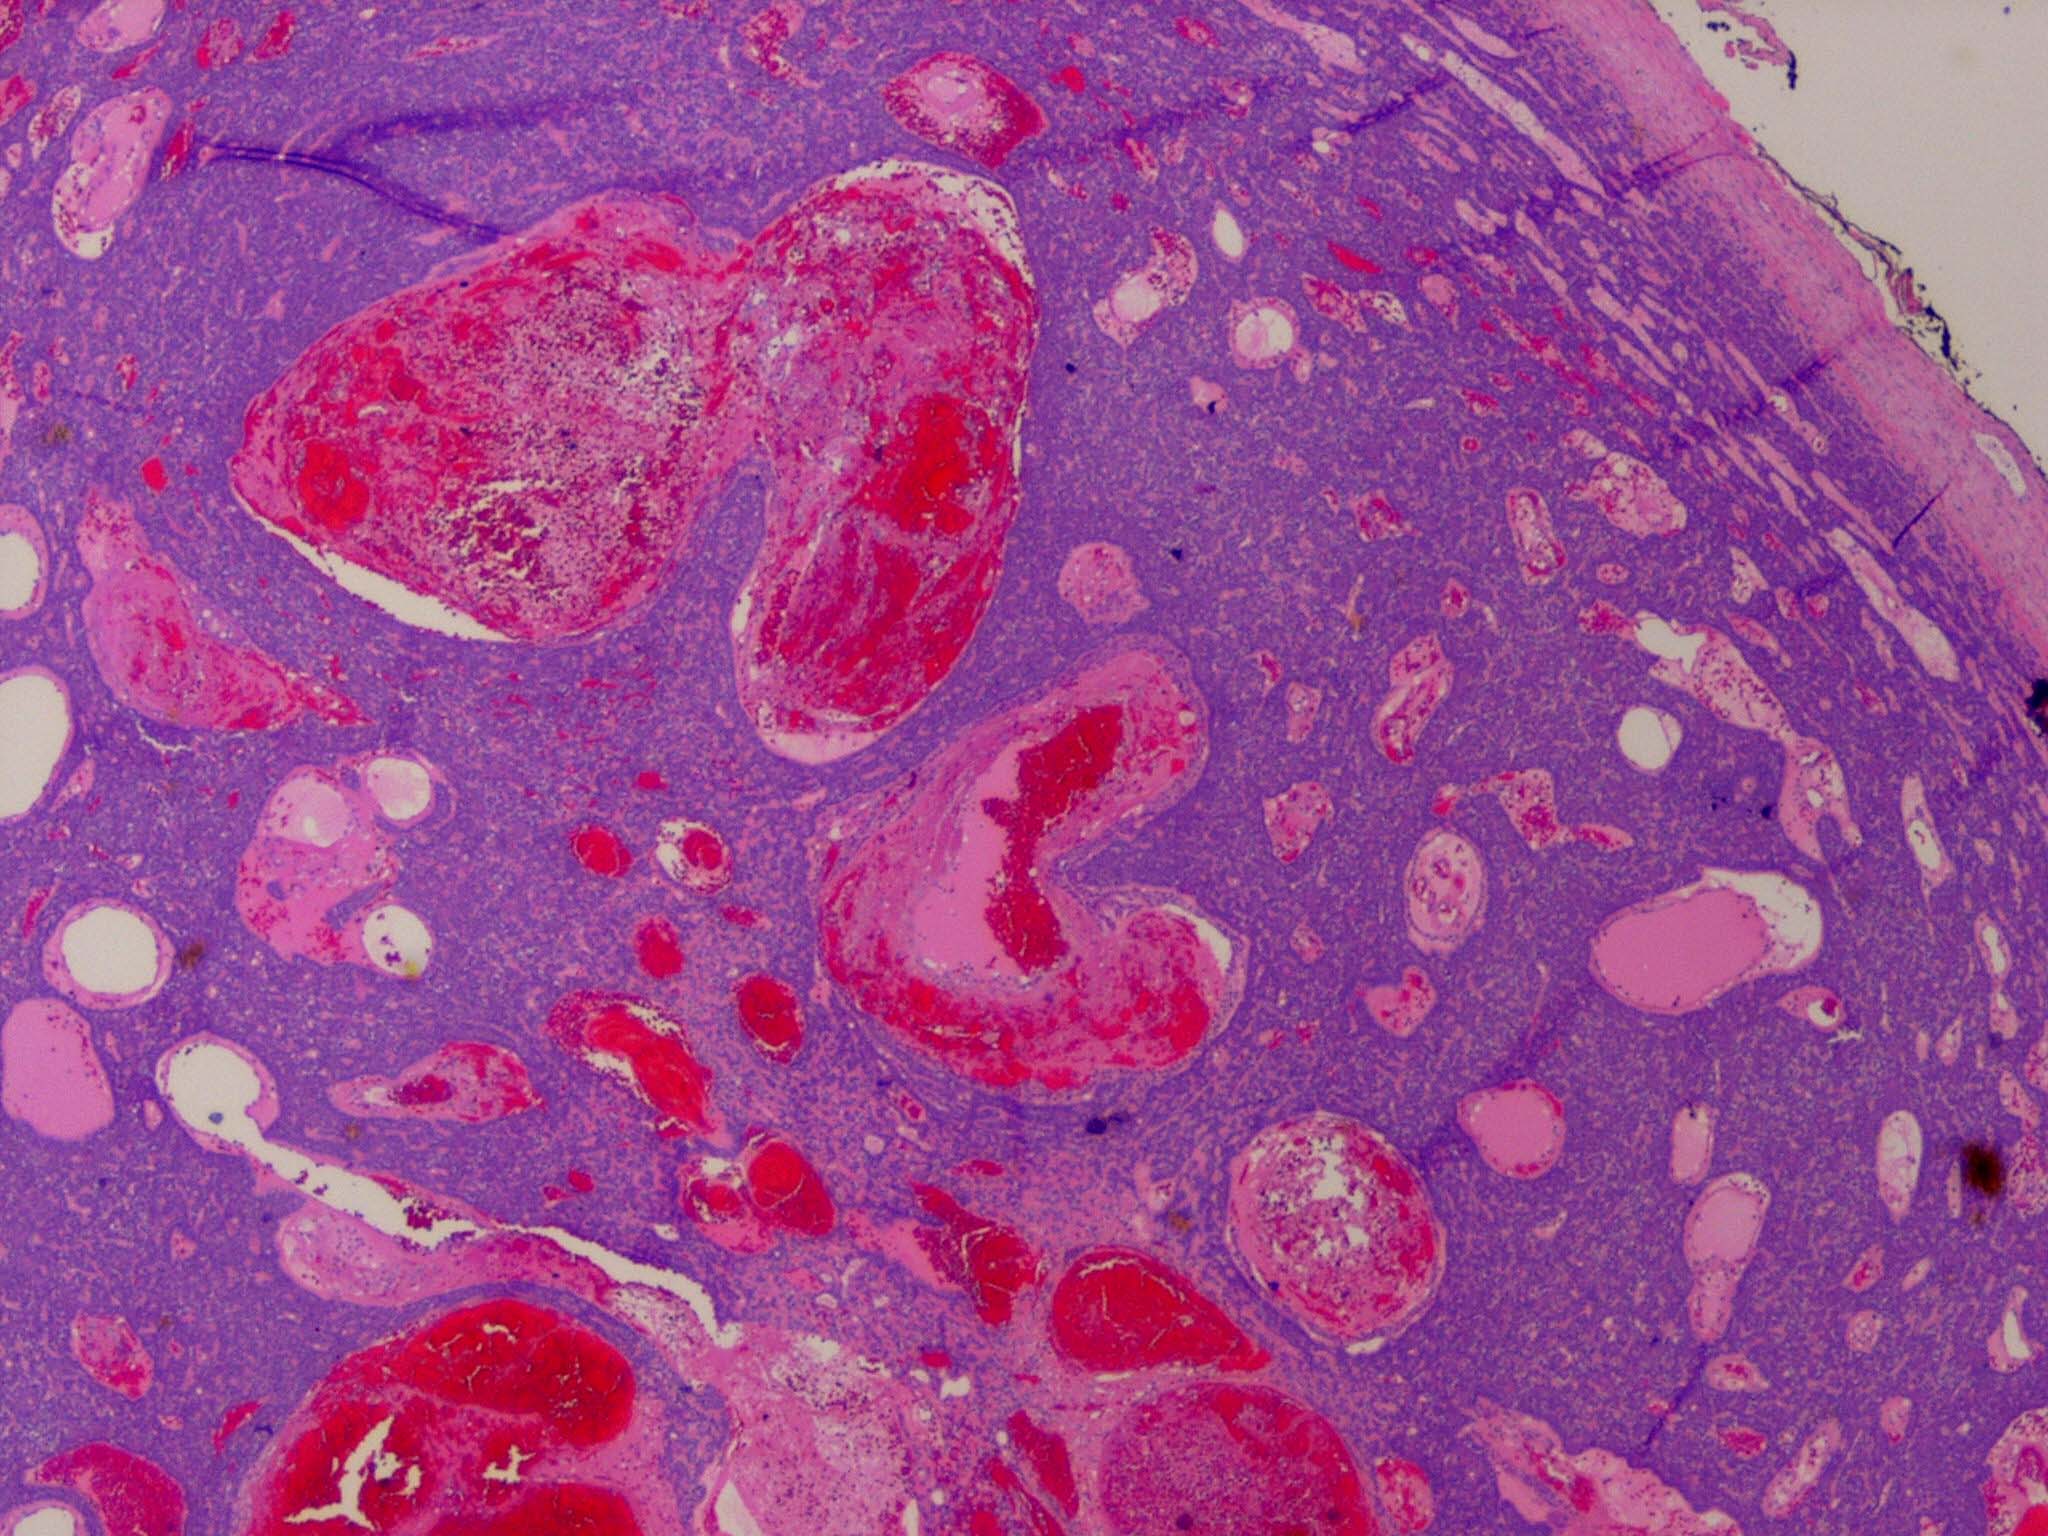

Spiradenoma=ورم غدي عرقي